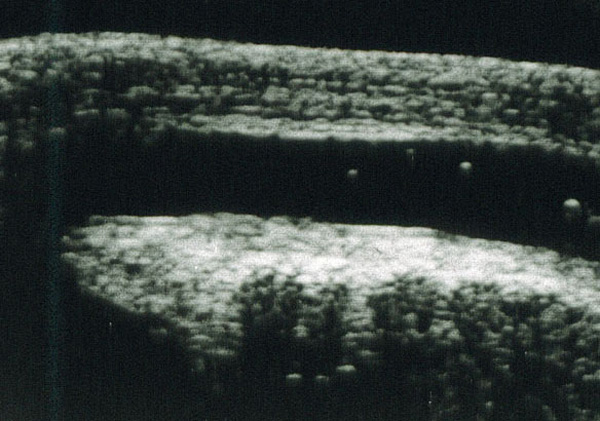

Urethral Ultrasonography

Urethral ultrasonography: This exam is performed using an auxiliary ultrasonic probe that is placed on the penis or perineum. It is a simple and entirely painless exam, which does not require any specific patient preparation.